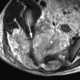

Local tumor extension